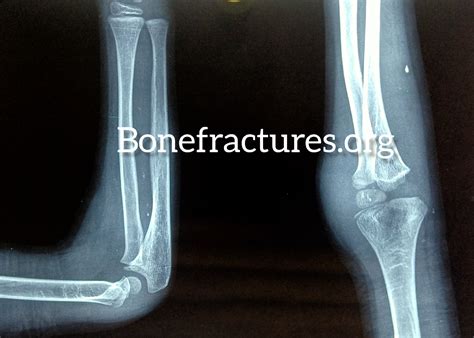

A non displaced fracture occurs when a bone breaks but the bone fragments remain in their original position. This type of fracture is often less severe than displaced fractures, where the bone fragments are misaligned. Non displaced fractures can occur in any bone in the body, but they are most commonly seen in the wrist, ankle, and spine. These fractures are typically the result of minor trauma, such as a fall or a direct blow to the bone.

Non displaced fractures are often classified based on the type of bone involved and the mechanism of injury. For example, a non displaced fracture in the wrist might occur due to a fall on an outstretched hand, while a non displaced fracture in the spine might result from a compression injury. Understanding the specific type of non displaced fracture is essential for determining the appropriate treatment and recovery plan.

• Imaging Studies: X-rays are the most common imaging tool used to diagnose non displaced fractures. They can provide a clear view of the bone and help determine the location and extent of the fracture. In some cases, additional imaging studies such as CT scans or MRI may be necessary to get a more detailed view of the injury.